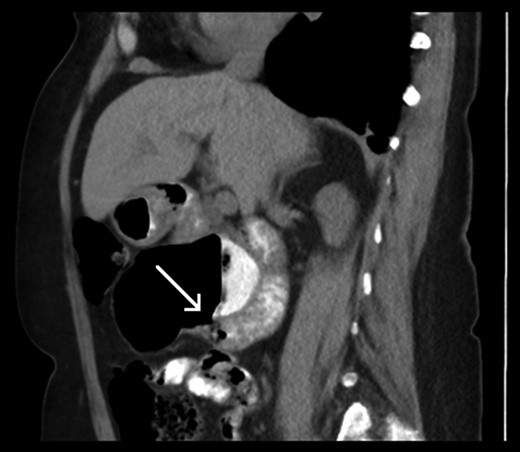

Sagittal slice of computed tomography (CT) scan—giant duodenal diverticulum partly filled with oral contrast. The arrow is indicating the neck of the diverticulum.

On investigation they be mistaken for abscesses with an air-fluid level or thought to be a separate loop of bowel [3]. As noted with our patient, she had multiple modalities of abdominal imaging that had not previously reported this diverticulum. Hers was thought to be asymptomatic and therefore did not need emergent management, however it should be kept in mind as a potential cause of acute abdomen in the future.